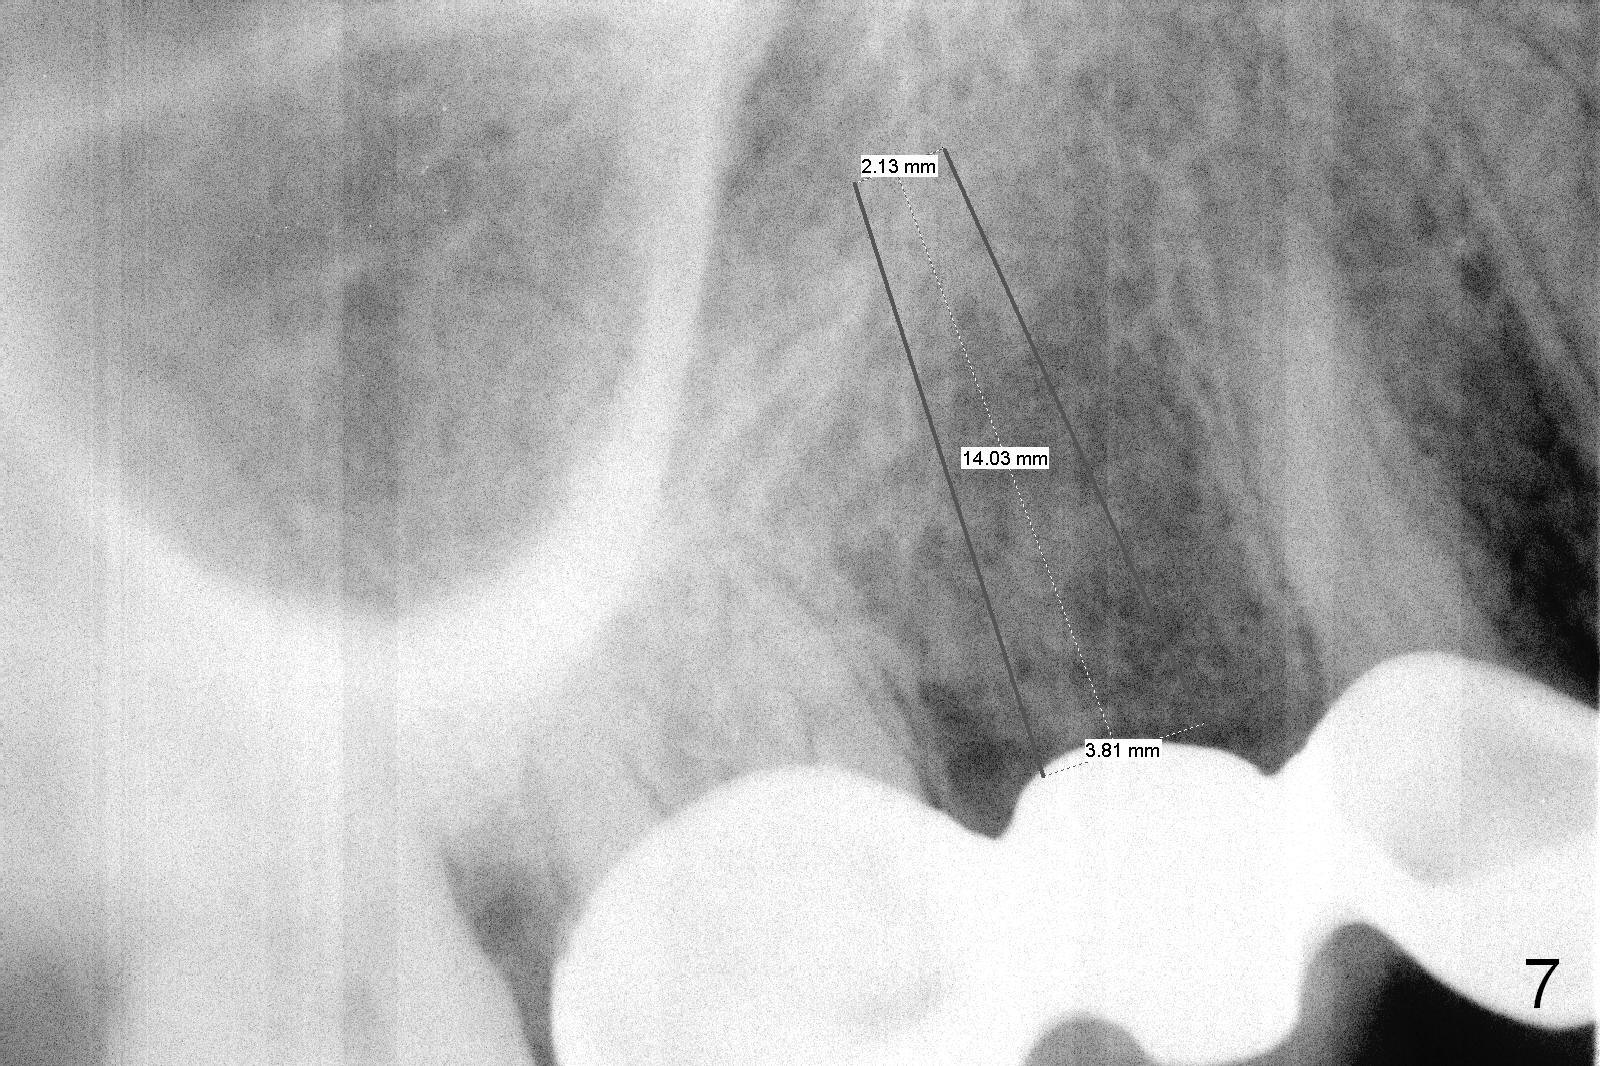

Ms. Li, a 34-year-old lady, had the upper right fixed partial denture made by an unlicensed dentist in California 10 years ago (Fig.1: #3-5). The gingival margin palatal to the retainers is erythematous (Fig.1 arrows). The patient's chief complaint is gum bleeding. The retainer at #3 is over-contoured buccopalatally (Fig.1, as compared to #14 in Fig.2), while the one at #5 is over-contoured buccopalatally and mesiodistally (compare to #12 in Fig.2). Panoramic X-ray (Fig.3), bitewing (Fig.4) and periapical film (Fig.5) all confirm that the bridge is over-contoured and that the retainers #3 and 5 have open margin (Fig.4 arrowheads). To improve oral hygiene and save the abutment teeth #3 and 5, it is in the patient's best interest to remove the bridge, place an implant at #4 and fabricate single-unit crowns at #3 and 5. Three to four months later, pyogenic granuloma develops between #4 and 5 (Fig.6 *) with generalized gingival erythema apically. The pontic at #4 and the retainer at #5 are to be removed first. An implant will be placed at #4 (Fig.7) with conjoined provisional at #4 and 5. The initial depth of osteotomy is 13 mm with Sinus Master Kit.